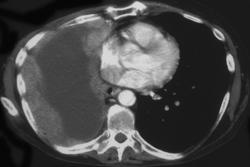

Pneumothorax S/P Lung Biopsy